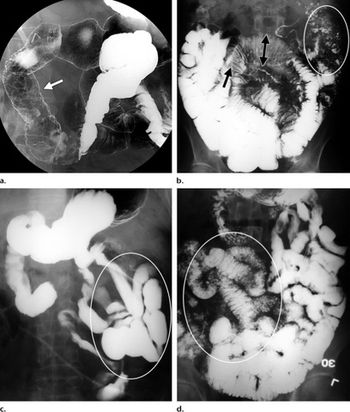

A formidably named bit of technology can open a new window into pancreas function, according to a new study in the journal Radiology. Serial magnetic resonance cholangiopancreatography (MRCP) with a spatially selective inversion-recovery (IR) pulse can provide insights into pancreatic flow noninvasively, Japanese researchers reported.